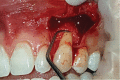

Gingival recession is an oral health problem that affects a large part of the population. Several treatments are suggested in the current literature; among them is the use of buccal fat pad grafting. The objective of this case report is to describe the treatment of a Miller Class I gingival recession using a nonpedicled buccal fat pad graft immediately after performing the surgery for buccal fat pad removal (bichectomy technique). First, bilateral surgical removal of the buccal fat pad was performed with the main objective of eliminating oral mucosa biting. The recipient site was prepared to receive a portion of the fat pad that was cut and macerated in a size that was sufficient to cover the recession. The patient was followed up at 15, 30, 60, and 365 days postsurgery, and the results showed an elimination of the oral mucosa biting and complete coverage of the gingival recession. It was concluded that the nonpedicled buccal fat pad graft is another option for the treatment of Miller Class I recessions.